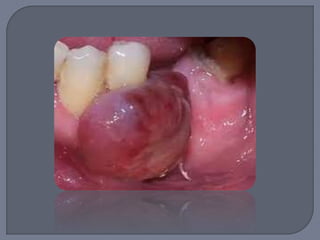

No representa una verdadera

neoplasia

Lesión reactiva causada por

irritación local o trauma

Anteriormente llamado

“granuloma reparativo de

células gigantes”

o Exclusivamente en encía o sobre borde alveolar

edéntulo

o Masa nodular de color rojo-azulado

o Sésil o pediculado

o Ulcerada o no

o Alrededor de 2 cm de

diámetro

Apariencia similar a granuloma

piógeno pero más violáceo

Se desarrolla a cualquier edad

Ligera predilección por los 50 y

60 años

60% de los casos en mujeres

Llega a haber reabsorción de

hueso subyacente

Escisión quirúrgica local por debajo del hueso

subyacente

Rebajar cuidadosamente el diente adyacente

para minimizar recidiva